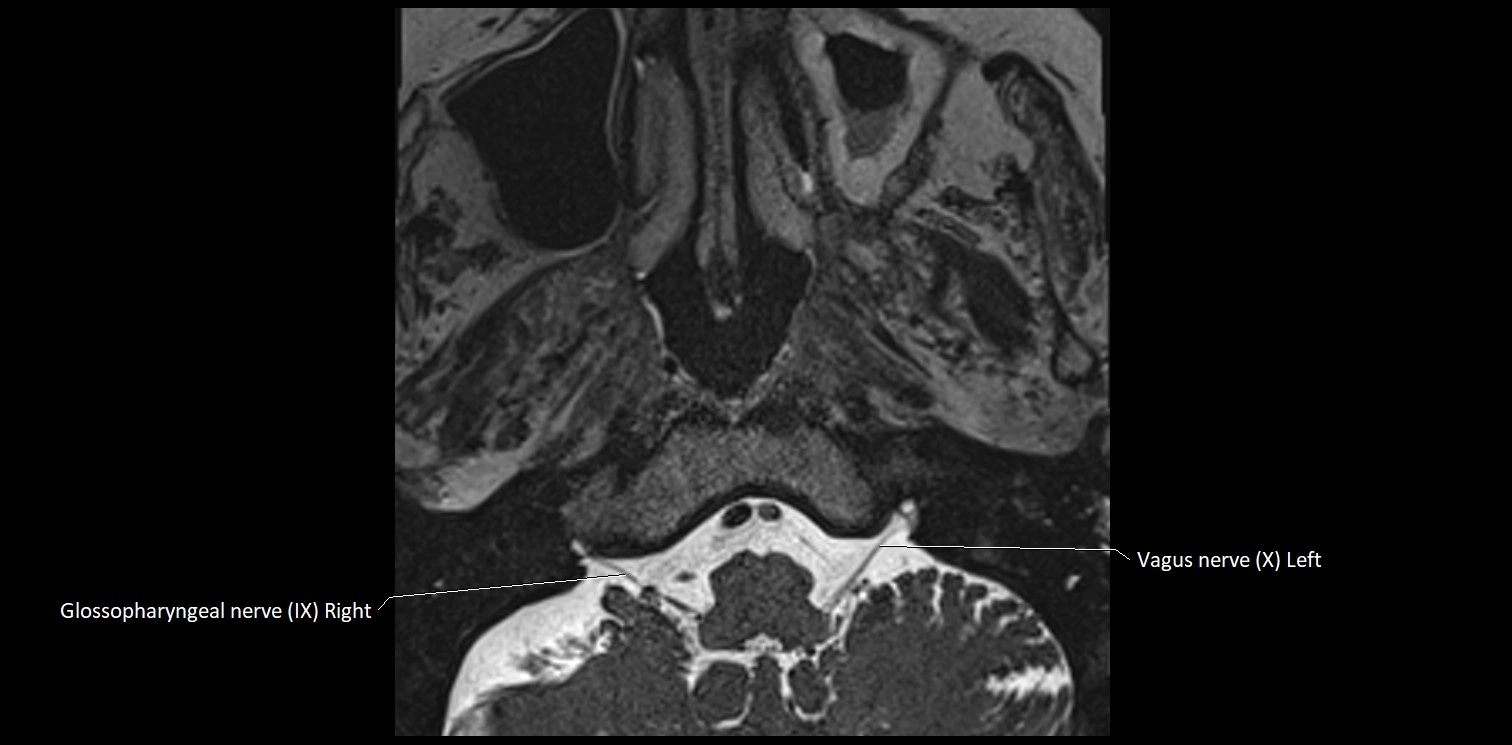

MRI images

image